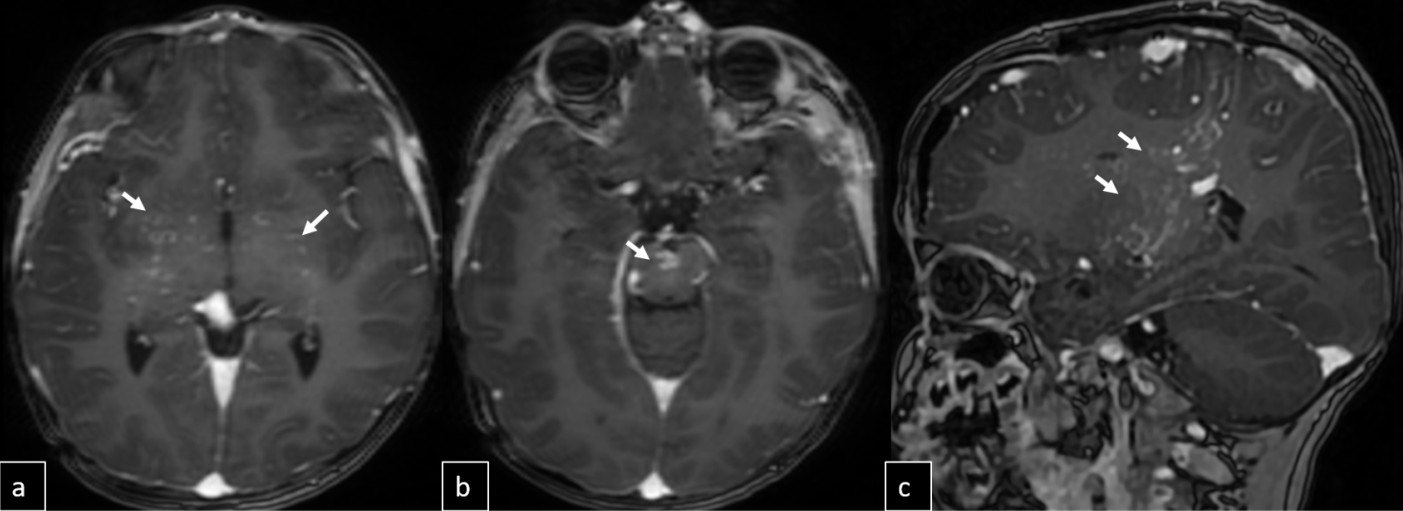

Cranial MRI demonstrated a dilated tortuous arteriovenous malformation in the right frontal lobe, fed by the distal branches of the anterior cerebral artery (ACA), draining into the cortical veins and central nervous system. A second AVM was detected in the corona radiata, with dilated parietotemporal draining veins fed by perisylvian branches of the middle cerebral artery (MCA), draining into the internal cerebral veins and the straight sinus via pericallosal dilated venous structures (Figure 2, Figure 3, Figure 4). At the level of the basal ganglia and mesencephalon, arterial angiomatosis resembling the classic “moyamoya” appearance was observed (Figure 5).

Digital subtraction angiography (DSA) confirmed the presence of two AVMs: one fed by distal branches of the right ACA and draining into the superior sagittal sinus, and another fed by MCA branches, draining into the internal cerebral vein. Capillary anastomoses were noted between the two AVMs. Selective bilateral internal carotid artery (ICA) injections revealed globally abnormal, tortuous arteriolar networks with delayed capillary filling, more pronounced on the right side (Figures 5, Figure 6, Figure 7). Based on these findings and the revised 2021 diagnostic criteria, the patient was diagnosed with MMD—characterized by stenosis of the intracranial ICA, narrowing at the terminal portion, and the development of abnormal collateral networks in the basal ganglia and periventricular white matter.4